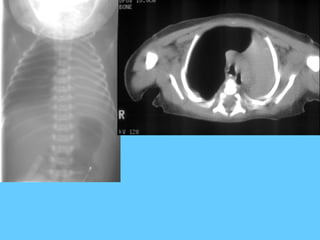

Pulmonary haemosiderosis

13-year-old girl who presented with haemoptysis. Admission film (a) shows

acute alveolar shadowing. b. Repeat film 3 days later shows improvement

in the alveolar oedema but there is now a reticular nodular pattern

developing. A diagnosis of pulmonary haemosiderosis made by

bronchoalveolar lavage. c. CT scan done during the recovery phase

demonstrates airspace shadowing, particularly in the left lung.